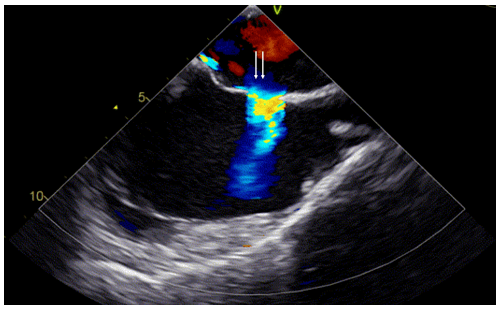

"贞"心一"课"|马凡综合征bentall术后的pfo封堵1例_患者_结构性_心脏